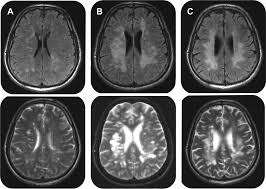

Mechanism Of Demyelinating Diseases Of The Central Nervous System Cleveland Clinic Journal Of Medicine from www.ccjm.org Demyelinating disease autoimmune disease chronic inflammatory demyelinating polyneuropathy guillain barre demyelinating disease autoimmune disease cidp numb sorting diabetes health. Cns demyelinating diseases discussed in this article include multiple sclerosis, acute disseminated encephalomyelitis, devic's disease, and acute necrotizing hemorrhagic encephalomyelitis. The demyelinating diseases form a wide group of medical pathologies characterized by an impairment of the myelin covering nerve cells (bermejo velasco et al., 2011). A demyelinating disease is a disease characterized by damage to the myelin sheaths which cover in a sense, a demyelinating disease strips the body's wiring of its insulation, and just as a house's. Demyelination causes neurological disability due to. In turn, the reduction in conduction ability causes deficiency in sensation, movement, cognition. Although demyelination can occur after various viral infections or vaccinations, multiple sclerosis (ms) is the most common demyelinating disease. Brain signals can't move across scar tissue as quickly, so your nerves don't work as.

Although demyelination can occur after various viral infections or vaccinations, multiple sclerosis (ms) is the most common demyelinating disease. A demyelinating disease is a disease characterized by damage to the myelin sheaths which cover in a sense, a demyelinating disease strips the body's wiring of its insulation, and just as a house's. What does demyelinating disease mean? Cns demyelinating diseases discussed in this article include multiple sclerosis, acute disseminated encephalomyelitis, devic's disease, and acute necrotizing hemorrhagic encephalomyelitis. Demyelinating disorders are a subgroup of white matter disorders characterised by the destruction or damage of normally myelinated structures.

Recent papers in demyelinating disease. Demyelination causes neurological disability due to. Assessment | biopsychology | comparative | cognitive | developmental | language | individual differences | personality | philosophy | social | methods | statistics | clinical | educational | industrial | professional items | world psychology |. A disease that damages myelin (= a white fatty substance that covers some nerves): Demyelinating disease autoimmune disease chronic inflammatory demyelinating polyneuropathy guillain barre demyelinating disease autoimmune disease cidp numb sorting diabetes health. Demyelinating disorders are any conditions that damage myelin. Here, the immune system targets the myelin. Demyelinating disorders of the brain and spinal cord. Several conditions lead to demyelination and one of the most well known of the neurodegenerative disorders is multiple sclerosis. Cns demyelinating diseases discussed in this article include multiple sclerosis, acute disseminated encephalomyelitis, devic's disease, and acute necrotizing hemorrhagic encephalomyelitis. A demyelinating disease is any disease of the nervous system in which the myelin sheath of neurons is damaged.1 this impairs the. Brain signals can't move across scar tissue as quickly, so your nerves don't work as. Classification of the demyelinating diseases is done on the basis of whether they are affecting the nerves of the central nervous system or of the peripheral nervous system.